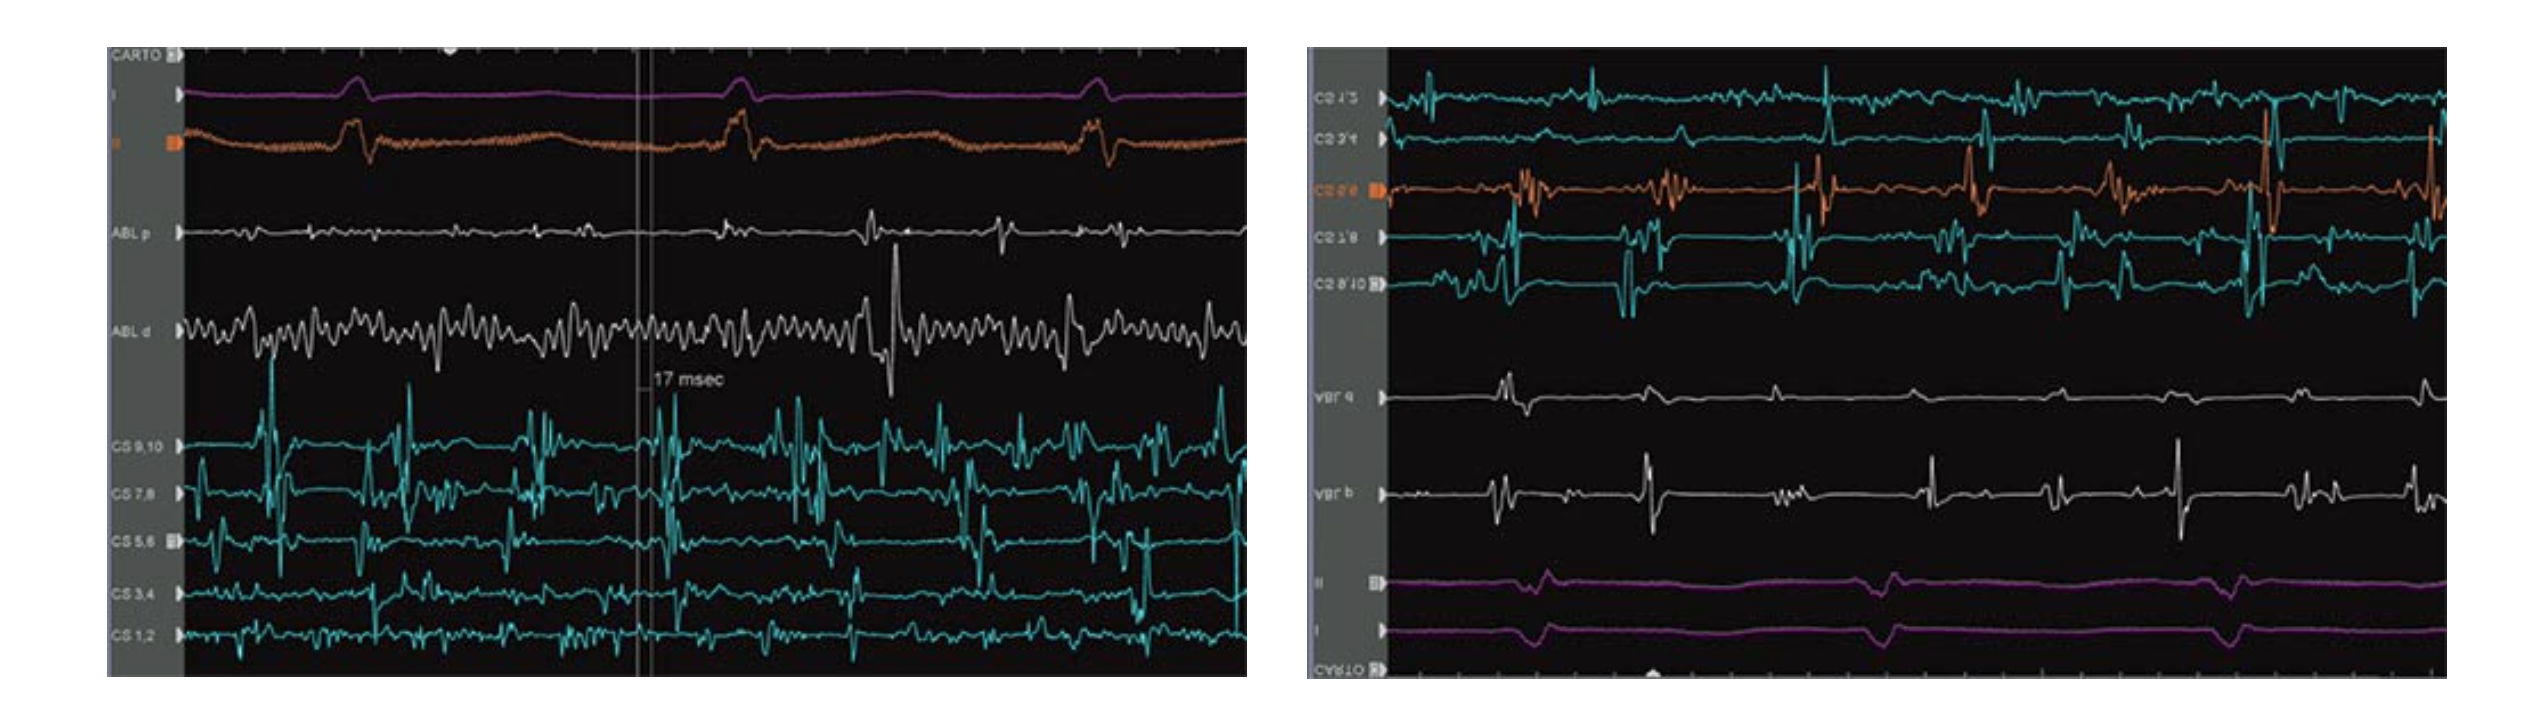

Shunyata laver ikke kun strømudtag som Hydra Delta-boksen. Clear Image Scientific er et søsterselskab, der fremstiller kabler og strømstyring til medicinsk udstyr, hvor det er afgørende, at man kan aflæse data som hjerterytme uden interferens eller støj på signalet.

Derfor er flere af Shunyatas strømkabler næsten identiske med de CIS-produkter, der bruges på hospitaler, bare betrukket med en sort strømpe på ydersiden.